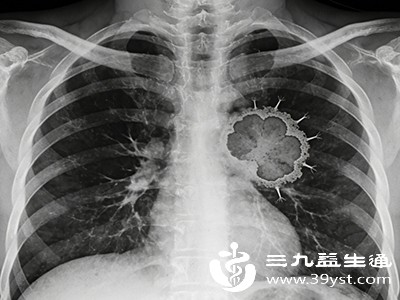

3.肺部肿瘤

对于肺部的肿瘤,胸片可发现肺部的肿块影。虽然胸片对早期微小肿瘤的检出率不如CT,但能初步提示肺部是否存在占位性病变,为进一步检查(如CT、活检)提供线索。